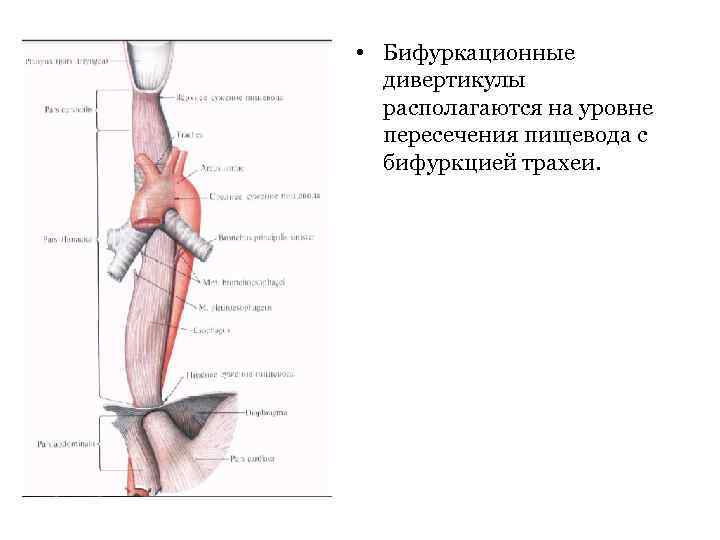

• Трансплевральный доступ Для доступа к грудному отделу – трасплевральная переднебоковая правосторонняя торакотомия, т. к. слева расположены дуга и нисходящий отдел грудной аорты. Показания: бифуркационные дивертикулы пищевода, медиастинит.

• Трансплевральный доступ Для доступа к грудному отделу – трасплевральная переднебоковая правосторонняя торакотомия, т. к. слева расположены дуга и нисходящий отдел грудной аорты. Показания: бифуркационные дивертикулы пищевода, медиастинит.

• Бифуркационные дивертикулы располагаются на уровне пересечения пищевода с бифуркцией трахеи.

• Бифуркационные дивертикулы располагаются на уровне пересечения пищевода с бифуркцией трахеи.